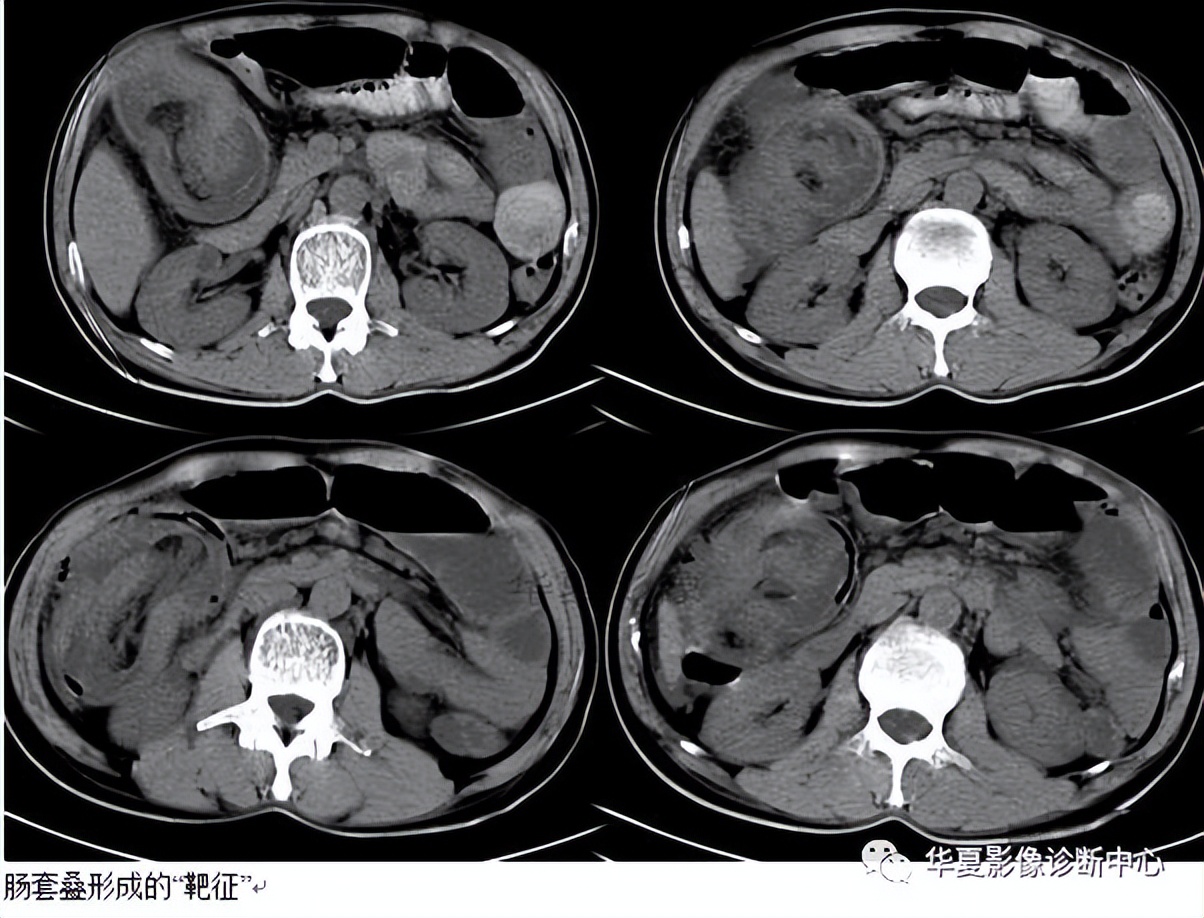

022:靶征(肠套叠)

是肠套叠最常见的特征性CT征像,为肠套叠长轴与CT扫描层面垂直时的表现,反映了套叠的各层肠壁、肠腔及肠系膜间的关系。典型排列为自外向内分别代表鞘部外层肠壁、鞘部肠腔内造影剂、鞘部内层肠壁、偏心性套入部肠系膜、套入部肠壁、套入部肠腔内造影剂。

肠套叠是指一段肠管及与其相连的肠系膜(套入部)被套如其相连的一段长管内(鞘部),导致肠内容物通过阻碍。婴儿由于大肠与小肠管径之比例相差大。故小肠易陷入大肠而被套牢。少数肠套叠可能来自某些器质性病变如美凯尔憩室、肠息肉、异位胰腺小结、血管瘤、异物、复制肠管、淋巴增生、肿瘤、寄生虫等,其中以美凯尔憩室最多,过敏性紫斑也常会合并肠套叠,大于2岁的小孩发生肠套叠,一定要考虑到这些病变。大于5岁的病例中,则以淋巴瘤为最多;成人肠套叠小肠多见,常伴发良性病变;结肠型肠套叠则更多由恶性病变继发。良性病变有脂肪瘤、平滑肌瘤、血管瘤、神经纤维瘤、腺瘤样息肉、美克尔憩室、术后粘连机场动力性病变等;恶性病变有转移瘤、腺癌、类癌、淋巴瘤及平滑肌肉瘤等。由于肠套叠长轴与CT扫描层面的角度不同,表现各异。如扫描层面和迂曲的肠道相平行时,表现为彗星尾征或肾形征:即套叠近端肠系膜血管牵拉聚拢的征象。